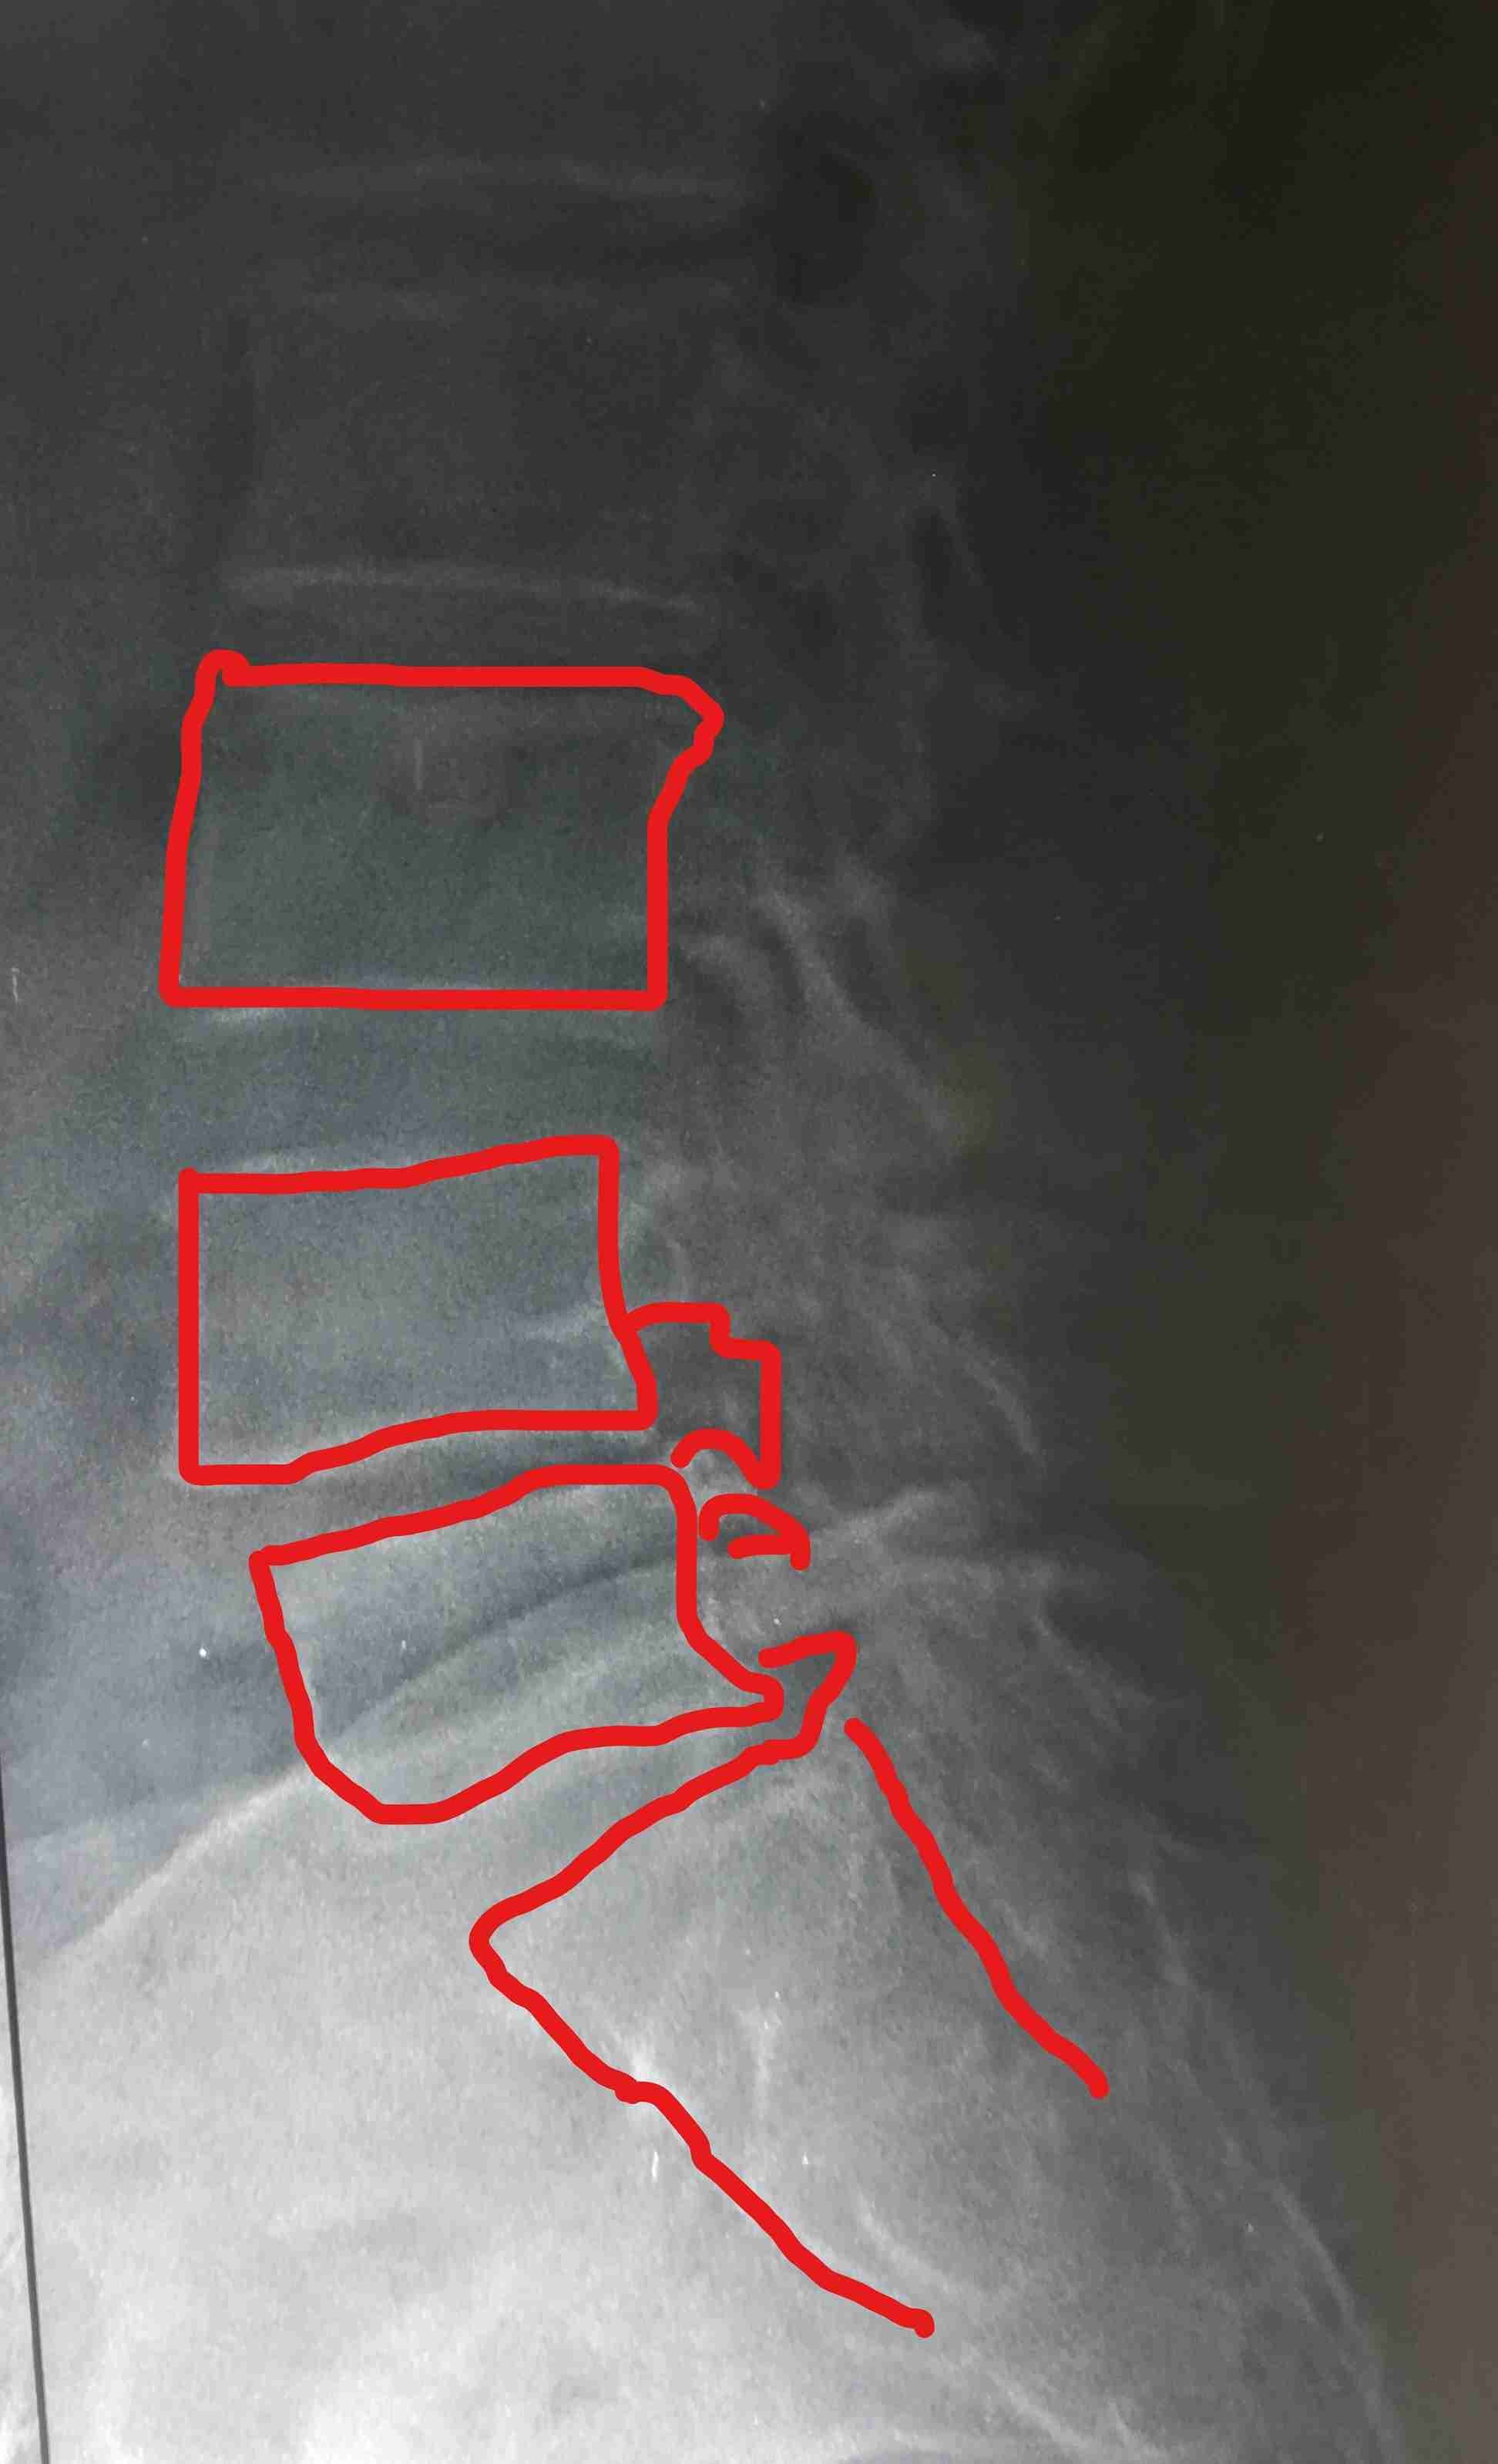

ضيق بالقناة العصبية القطنية مستويات متعددة مع تزحزح فقاري قبل وبعد الجراحة

multiple levels of lumbar nerve canal stenosis with spondylolisthesis before and after surgery

A successful surgery was performed to treat multi-level lumbar spinal stenosis accompanied by spondylolisthesis. This condition causes pressure on the nerves in the spinal column, leading to severe pain and difficulty in movement.